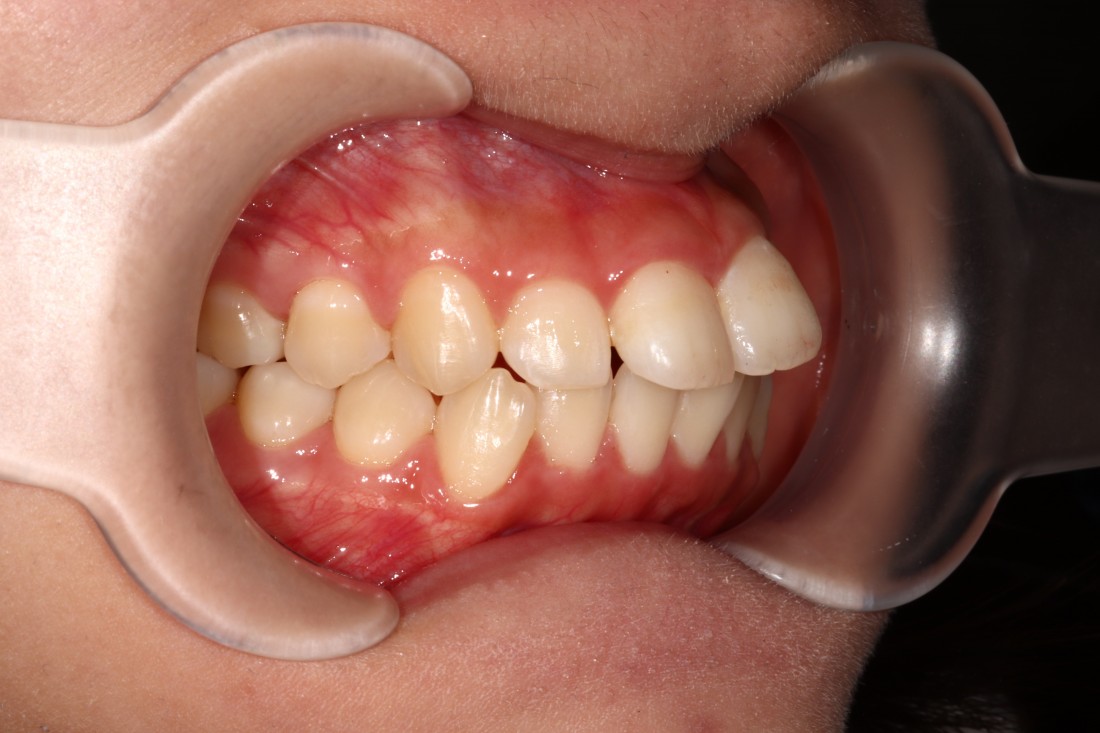

광주 성인 교정치과에서

충치치료와 교정진료를 동시에 받으신

성인 여성 환자분의 케이스입니다.

충치치료 전에는 은색 보철물이 있던 자리에

교정진료의 마무리와 동시에

치아색 보철물을 씌워서

치아교정 + 충치치료를 동시에 진행하였습니다.

광주 성인 치아교정의 경우

충치치료의 시기를 잘 판단하여

성공적인 진료를 완성할 수 있기 때문에

분과별 전문의가 협진하는

광주 성인 교정치과를 선택하시는 것이 좋습니다.